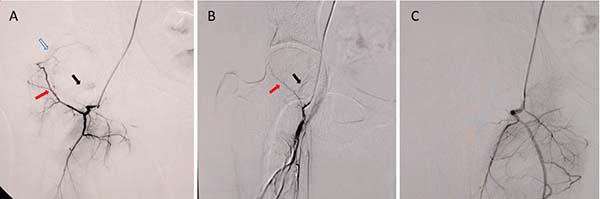

③股骨头血运情况:

除了常规评估股骨头坏死的分期分型外,对股骨头坏死进行数字减影血管造影(digital subtraction angiography, DSA),根据血管的分支情况进行不同的分型,来评估坏死股骨头的血运状态,为精准治疗方案的选择及预后预测提供客观依据:

图A可见旋股内动脉(红色箭头)、上支持带动脉(白色箭头)与下支持带动脉(黑色箭头)均显影,表明股骨头血运状态良好;图B可见旋股内动脉显影较淡薄(红色箭头),上支持带动脉未显影,仅下支持带动脉显影(黑色粗箭头),表明血运状态一般;图C可见旋股内动脉及上、下支持带动脉均未显影,表明股骨头血运状态较差